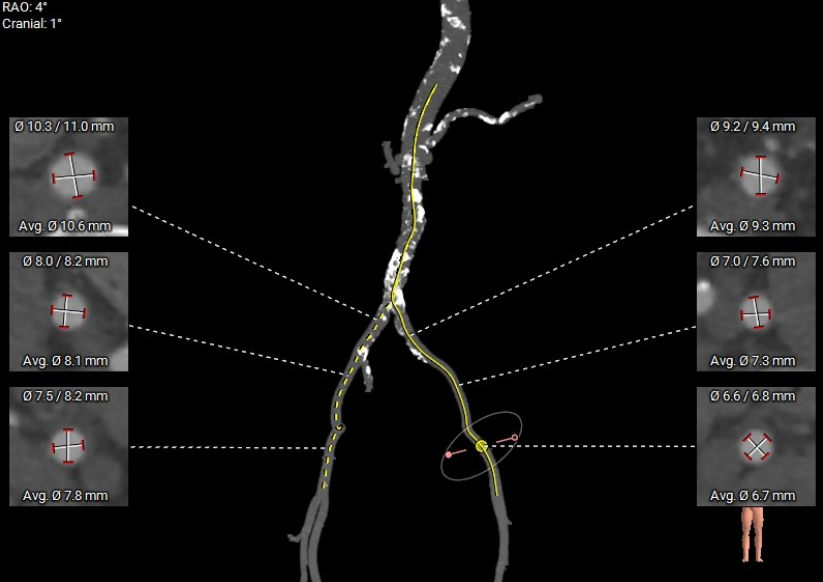

外周血管及主动脉弓形态:

主动脉弓角度62°,散在钙化

入路血管走形良好,双侧股髂动脉内径可

• 双侧外周血管走行正常,存在散状钙化,迂曲钙化尚可,整体入路条件可。